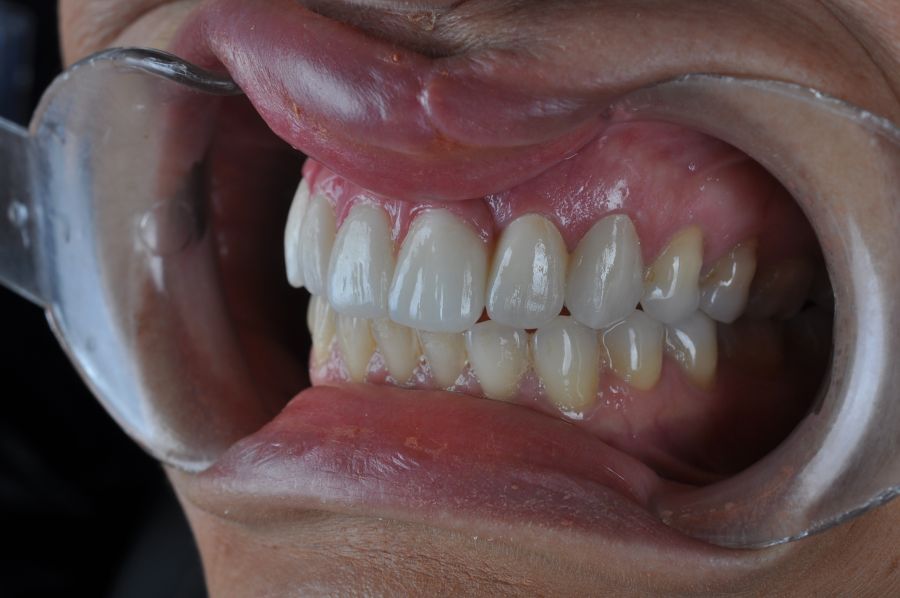

El día de la colocación de las estructuras, se arenó el interior de las coronas dentosoportadas con óxido de aluminio de 50 m y fueron cementadas con cemento de resina Multilink Ò. El puente implantosoportado se atornilló al torque indicado (20Nw) (Figuras 14, 15, 16 y 17).

La evolución postoperatoria fue favorable, sin complicaciones quirúrgicas. La paciente mostró una correcta cicatrización de los tejidos blandos tras la resección quirúrgica. A los 30 días de la cirugía, se inició el tratamiento con radioterapia adyuvante, completando un total de 30 sesiones sin incidencias relevantes.

Finalizado el tratamiento oncológico y confirmada la ausencia de enfermedad activa, se procedió a la segunda fase quirúrgica con la colocación de pilares transepiteliales Multiunit®. La integración de los implantes cigomáticos y del implante endoóseo fue satisfactoria, observándose estabilidad clínica y ausencia de signos de periimplantitis.

Las impresiones analógicas y el posterior flujo digital permitieron una correcta planificación protésica. Las estructuras definitivas, confeccionadas en óxido de zirconio monolítico sobre interfases metálicas de titanio, mostraron una adecuada adaptación pasiva tanto clínica como radiográficamente. La prueba estética permitió ajustes oclusales y funcionales mínimos, optimizando el resultado final.

En enero de 2021, el puente implantosoportado fue atornillado con un torque controlado (20 Nw), y las coronas dentosoportadas cementadas con éxito. La paciente refirió una notable mejoría en la función masticatoria, fonación y estética facial, manifestando un alto grado de satisfacción.

En el seguimiento a 4 años tras la colocación de la prótesis definitiva, no se observaron complicaciones mecánicas ni biológicas. La paciente continúa libre de enfermedad y con una correcta adaptación al tratamiento rehabilitador implantosoportado (Figura 18).